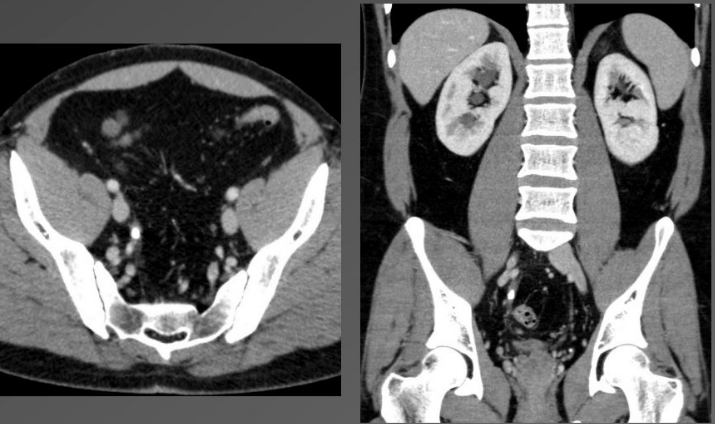

Visualização anatômica do abdômen em tomografia computadorizada (Fonte: Radiology Key)